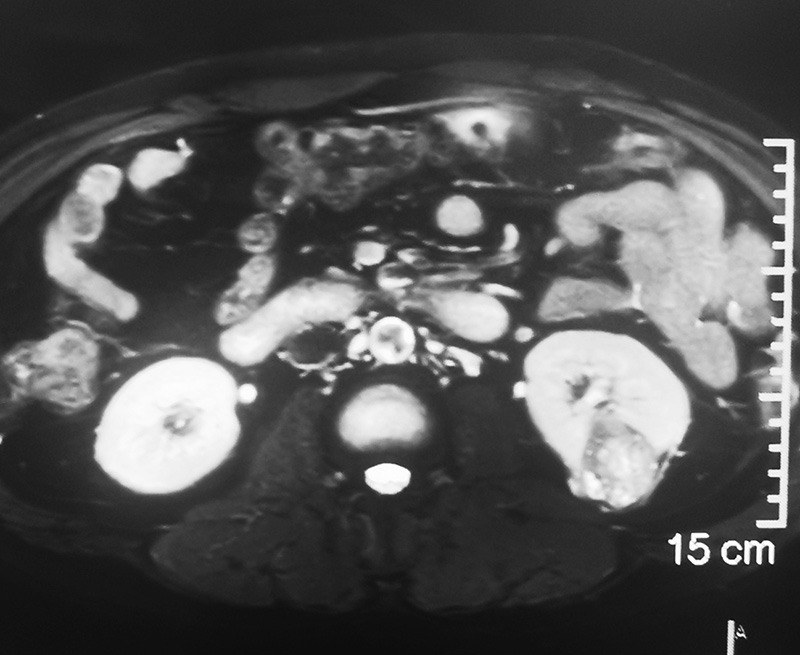

腹部CT显示“左肾肿瘤”

泌尿外科郑凯主任看过吴先生的影像资料后,考虑该肿瘤为恶性,需手术治疗。随后,郑凯主任组织全科医师进行术前病例讨论,肿瘤体积为3x4x3cm,适合行保留肾脏的肿瘤切除术——肾部分切除术。郑凯主任随后患者及家属沟通:吴先生的肿瘤发现比较早,这是不幸中的万幸,需及早手术根治肿瘤,还可以保住左侧肾脏。不然,随着肿瘤增大,全切左肾,可能导致肾功能下降,从而增加慢性肾病风险。专家团队科学的分析及建议,再加上患者了解到的郑凯主任团队资历深厚,马上决定接受手术治疗。